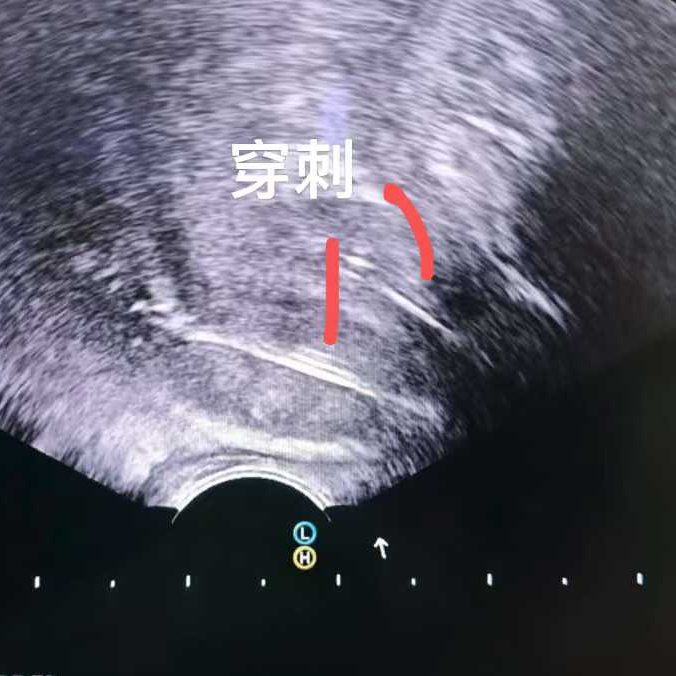

比如這位馬來西亞患者,PSA指標正常,但影像卻發(fā)現(xiàn)可疑病灶,結(jié)果穿刺證實是少見的前列腺尿路上皮癌,在我院接受了冷凍消融治療。